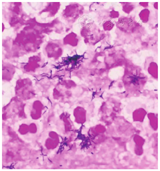

患者男,59岁,因"突发左上肢无力30 h"于2022年3月28日收入丽水市中心医院。患者30 h前在家中无明显诱因下突发左上肢无力,不能持物,伴头晕,无头痛,言语及行走如常,休息无好转,当时未重视,未诊治,症状无缓解。既往有下肢静脉血栓病史,脑动脉瘤手术史;高血压病史多年,氨氯地平片10 mg/次(1次/d)规律服药。入院体格检查:意识清楚,体温为36.8 ℃,脉率为99次/min,呼吸频率为20次/min,血压为170/96 mmHg(1 mmHg=0.133 kPa);双侧瞳孔等大等圆,对光反射灵敏,无眼震,双侧鼻唇沟对称,伸舌居中,左上肢肌力Ⅱ级,左下肢肌力Ⅳ级,右侧肢体肌力正常,四肢肌张力正常,左侧巴宾斯基征(+)。入院当天实验室检查示:白细胞计数为7.1×109/L,中性粒细胞比例为0.763,淋巴细胞比例为0.176,血红蛋白为165 g/L,血小板计数为174×109/L;快速超敏CRP为5.91 mg/L,降钙素原为0.04 μg/L,白蛋白为33.4 g/L,血钙为2.09 mmol/L;血脂、血糖、尿常规、粪便常规未见异常。3月28日头颅MRI检查示右侧额叶见一片状不规则肿块(图1),大小约2.3 cm×1.4 cm×1.8 cm,弥散明显受限,双侧侧脑室旁白质区多发腔隙性脑梗死,部分软化灶;动脉瘤术后;右侧额窦、双侧上颌窦炎症。予氨氯地平片10 mg(1次/d)降压、阿托伐他汀钙片20 mg(1次/d)调脂稳斑等对症治疗。4月1日,患者偶感头晕、头痛,体格检查:左上肢肌力0级,左下肢肌力0级,右侧肢体肌力Ⅴ级,四肢肌张力正常,左侧巴宾斯基征(+);头颅MRI增强检查示右侧额叶占位,团片状病灶增大,约4.5 cm×2.4 cm×2.1 cm。因左侧肢体无力进展较快,考虑脑脓肿,于当天行头颅引流手术,抽出黄色浓稠脓液约15 mL,脓液送细菌涂片及细菌培养检查,涂片检出革兰阴性杆菌和革兰阳性球菌(图2)。脑脓肿诊断明确,予美罗培南针2.0 g/次(每8 h 1次)静脉滴注联合万古霉素针1.0 g/次(每12 h 1次)静脉滴注,以及阿米卡星20 mg/次(1次/d)注入脓肿腔治疗。4月4日,脓液厌氧培养出5种细菌,经质谱鉴定为直肠弯曲菌、具核梭杆菌、微小微单胞菌、牙龈卟啉单胞菌和福赛斯坦纳菌;直肠弯曲菌及厌氧菌的药物敏感试验困难未检测。4月8日,脑脓肿脓液宏基因组学二代测序结果提示直肠弯曲菌(特异序列数为2 826)、具核梭杆菌(特异序列数为59 904)、微小微单胞菌(特异序列数为25 246)、牙龈卟啉单胞菌(特异序列数为8 953)、龈沟产线菌(特异序列数为6 471)、福赛斯坦纳菌(特异序列数为3 673),证实直肠弯曲菌合并多种厌氧菌感染。4月13日,头颅MRI检查示脓肿周围水肿加重,感染科会诊后改用青霉素480万U/次(每6 h 1次)静脉滴注联合氯霉素1.5 g/次(1次/d)静脉滴注治疗脑脓肿,因丽水市中心医院氯霉素缺货,用青霉素480万U/次(每6 h 1次)静脉滴注联合奥硝唑0.5 g/次(每12 h 1次)静脉滴注治疗脑脓肿。2022年4月20日,改用青霉素480万U/次(每6 h 1次)静脉滴注联合氯霉素1.5 g/次(1次/d)静脉滴注治疗脑脓肿。5月8日,患者体温正常,无咳嗽、咳痰,无头痛、呕吐,炎症指标恢复正常,停用抗菌药物,予康复治疗。2022年5月20日,患者住院54 d,脑脓肿经切开引流后抗菌药物治疗38 d,康复治疗2周后能独立站,室内步行,炎症指标正常,病情稳定,予以出院。

直肠弯曲菌是弯曲菌属的一种,微需氧或厌氧生长,革兰染色阴性,弯曲呈弧形、S形或螺旋形杆菌,在陈旧的培养物中或长时间暴露在空气中可形成球形。直肠弯曲菌为口腔定植菌群的一种[1],其较少引起口腔外感染,主要从活动性牙周感染患者中分离,但也有肺部感染的报道[2],亦有在乳腺囊肿患者中分离到该菌的报道[3],但是直肠弯曲菌引起颅内感染的报道非常少[4]。具核梭杆菌为梭杆菌属的一种,是口腔的定植菌群之一,是革兰染色阴性、无芽孢的专性厌氧菌。具核梭杆菌不仅可引起口腔感染性疾病[5],还与大肠癌及脑、肝、肺、脾等脏器感染密切相关[6]。微小微单胞菌为革兰阳性专性厌氧球菌,是口腔的定植菌,是牙周炎主要可疑病原菌之一,其还与腹部脓肿、肝脓肿、心内膜炎、化脓性关节炎、脑膜炎、菌血症、根尖周炎及冠周炎等相关[7,8,9]。牙龈卟啉单胞菌、龈沟产线菌及福赛斯坦纳菌均为口腔定植专性厌氧菌,且为重要的牙周炎致病菌,在牙周疾病的发生和发展中起着重要作用[10,11,12,13]。本例患者为中年男性,既往有下肢静脉血栓病史、动脉瘤术后,本次在家中无明显诱因下突发左上肢无力,不能持物,伴头晕;头颅MRI检查发现右侧额叶见一片状不规则肿块,头颅手术引流抽出黄色浓稠脓液,脓液标本涂片检查见革兰阴性杆菌和革兰阳性球菌,脓液培养检出5种细菌,故细菌性脑脓肿诊断明确。

本例脑脓肿患者共检测到6种病原微生物,包括1种弯曲菌(直肠弯曲菌)及5种厌氧菌(具核梭杆菌、微小微单胞菌、牙龈卟啉单胞菌、龈沟产线菌和福赛斯坦纳菌)。患者的脓液标本涂片经直接显微镜下检查见到革兰阴性弯曲菌、革兰阴性杆菌及革兰阳性球菌,脓液标本培养结果为直肠弯曲菌、具核梭杆菌、微小微单胞菌、牙龈卟啉单胞菌和福赛斯坦纳菌,同时脓液标本宏基因组学二代测序检出直肠弯曲菌、具核梭杆菌、微小微单胞菌、牙龈卟啉单胞菌和福赛斯坦纳菌,说明这5种菌参与了脑脓肿的发病,是其致病菌。龈沟产线菌通过分子生物学方法检出,并未在厌氧培养中培养到,尚不能确定其是否参与脑脓肿的感染及其所起到的作用。近年来,宏基因组学二代测序技术不断发展,其灵敏度较高,为感染性疾病特别是疑难病例的病原学诊断提供了很好的辅助诊断方法,但仍需结合病原学检查结果及临床症状进行诊断。